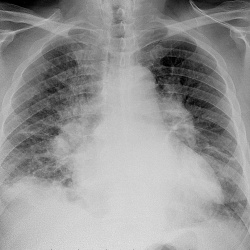

Пациента 70 лет. Две недели назад была температура , перенесла на ногах , что на снимке?